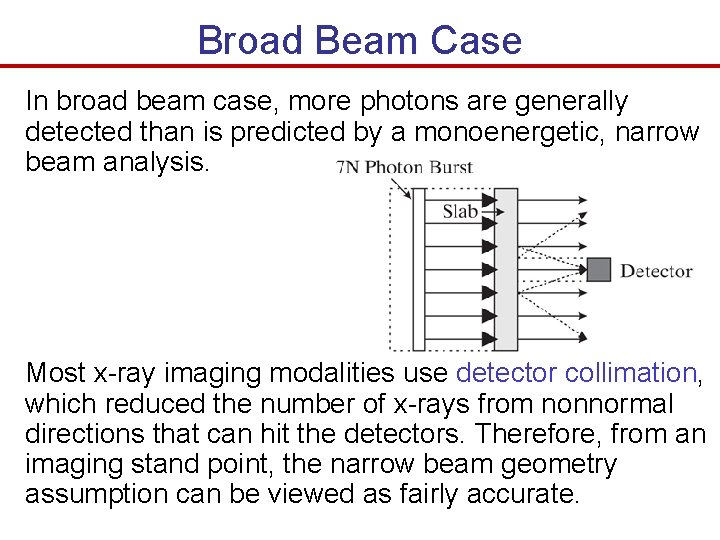

Broad Beam Case In broad beam case, more photons are generally detected than is predicted by a monoenergetic, narrow beam analysis. Most x-ray imaging modalities use detector collimation, which reduced the number of x-rays from nonnormal directions that can hit the detectors. Therefore, from an imaging stand point, the narrow beam geometry assumption can be viewed as fairly accurate.